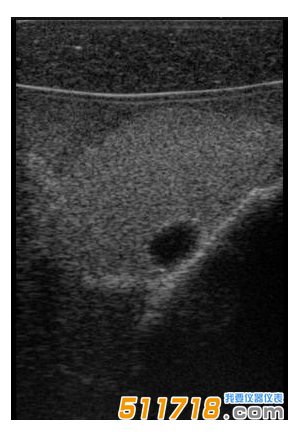

CIRS

074甲狀腺超聲訓(xùn)練模體包含一個(gè)略微擴(kuò)大的甲狀腺,位于一個(gè)擬人化的頸部。下巴和鎖骨被提供作為外部解剖標(biāo)志。體模提供氣管,頸內(nèi)靜脈和頸總動(dòng)脈作為內(nèi)部解剖標(biāo)志。每個(gè)甲狀腺葉包含一個(gè)囊腫和一個(gè)等回聲僵硬病變。可以在甲狀腺內(nèi)定制生產(chǎn)各種結(jié)節(jié)。*有材料都配制成超現(xiàn)實(shí)的。

略微擴(kuò)大的甲狀腺包含單個(gè)囊腫和每個(gè)葉中的一個(gè)等回聲,僵硬的病變。

可以對(duì)每個(gè)囊腫進(jìn)行細(xì)針抽吸。每個(gè)僵硬病變都設(shè)計(jì)用于超聲彈性成像的可視化,并且可以進(jìn)行活組織檢查。這些病變對(duì)甲狀腺是等回聲的并且具有標(biāo)準(zhǔn)的B模式成像。

單純囊腫